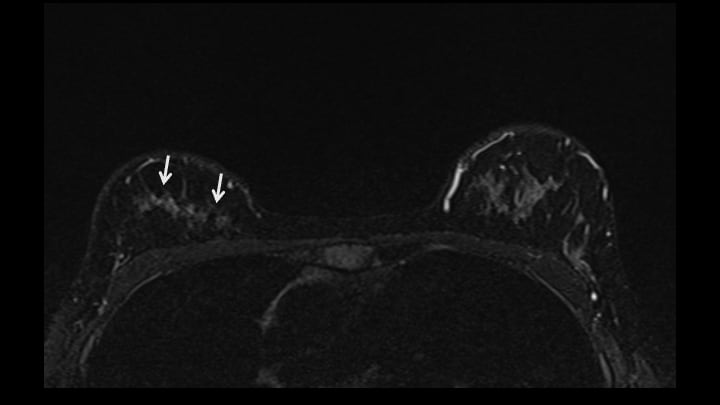

5. ダイナミックMRI 早期相

右乳腺上部にnon-mass enhancementを認める(矢印)。